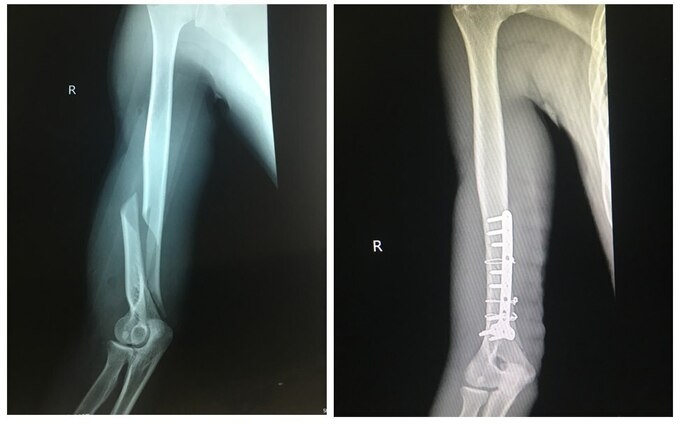

| Hình ảnh chụp X-quang cánh tay bị gãy trước và sau khi được nẹp đinh. (Ảnh: BVCC). |

Gia đình vội đưa đến cấp cứu tại Bệnh viện Việt Nam - Thụy Điển (Uông Bí). Sau khi tiến hành chụp X-quang, các bác sĩ xác định bệnh nhân bị gãy kín 1/3 dưới xương cánh tay phải. Bệnh nhân được chỉ định phẫu thuật nắn chỉnh xương và kết hợp xương nẹp vít.

Theo bác sĩ khoa Chấn thương - Chỉnh hình & Bỏng, khi tiến hành phẫu thuật, ê-kíp phát hiện lộ ổ gãy 1/3 dưới xương cánh tay phải, xương cánh tay bị gãy vặn xoắn đoạn chừng 8cm, di lệch nhiều, ổ gãy nhiều máu tụ. Ê-kíp phẫu thuật đã tiến hành làm sạch ổ gãy, đặt lại xương và cố định lại xương cánh tay bằng nẹp, vít.